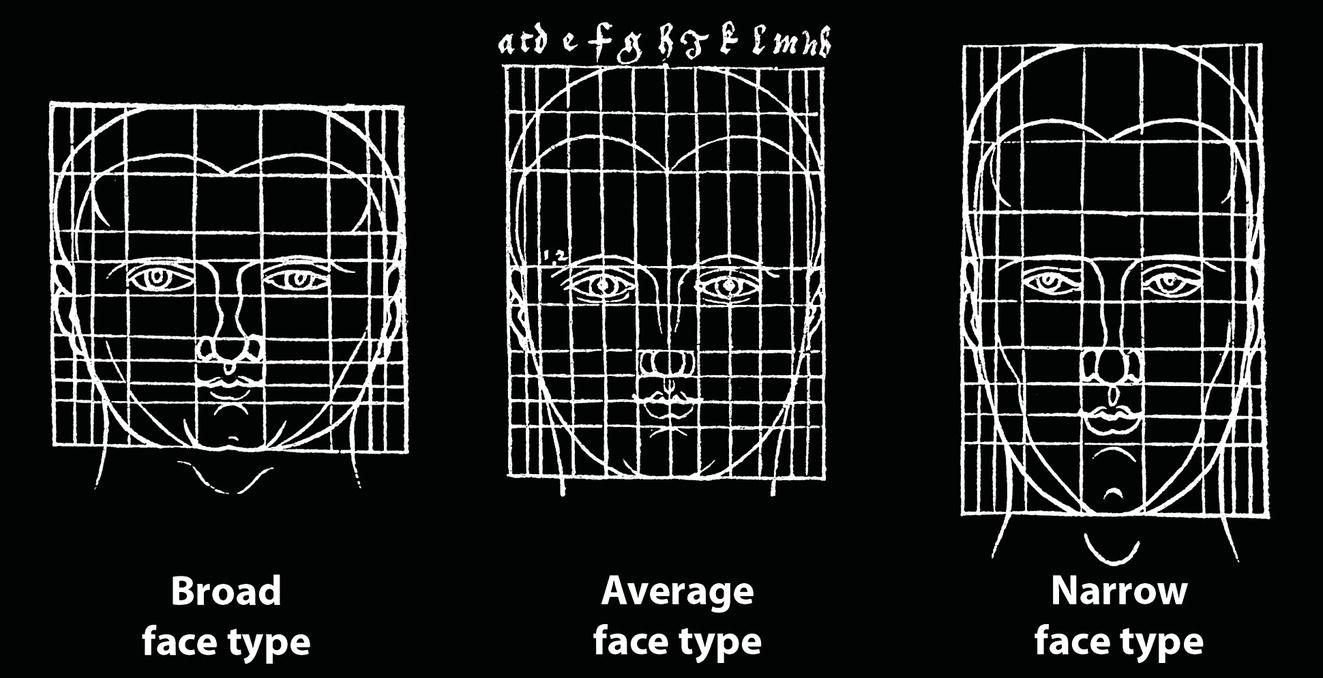

‘It is the common wonder of all men, how among so many millions of faces, there should be none alike’. Sir Thomas Browne (1605–82), English physician and writer, Religio Medici (1643)1 Individual variability is a fundamental principle in human biology. One of the most variable and distinguishable parts of the human body is the craniofacial complex. Clinicians will often compare a patient’s craniofacial measurements and proportions to the so‐called population norms (normative values) or even to classical ideals. However, Simon (1926) stated: ‘all we ever find are variations; an exact, ideal normal does not exist, cannot exist. And this is our enigma; in theory we will never find the normal, in practice we forever feel its need and apply it constantly’.2 The use of population norms may be logically enhanced by evaluating normal ranges of variability. Therefore, clinicians must have a thorough understanding of the normal ranges of variability in every aspect of craniofacial form, depending on age, sex and ethnic variability. Developmental disorders, as well as traumatic injuries and pathological conditions, may lead to deformities of the head and the face. Therefore, clinicians need to have a thorough understanding of the normal anatomy and morphological range of variation of the craniofacial complex in both males and females of different ages and ethnic groups, to act as guidelines when treatment planning the restoration of normal craniofacial proportions. Classifications that are useful for descriptive purposes include: A proportion index provides a numerical expression of the proportionality of a region of the craniofacial complex. The use of proportion indices dates back through the history of craniometry, particularly in the late nineteenth century. Linear (chord) or surface (arc) distances of the skull were measured between a variety of defined craniofacial landmarks; with any two measurements, the smaller was expressed as a percentage of the larger in order to provide a proportion index value. These could be used to provide an indication of skull shape. Figure 8.1 Determination of the normality or abnormality of any craniofacial measurement (or proportion index value) obtained from patients may be evaluated by comparison with the normative values obtained from a normal (average representative) population sample. The normal range of measurements is provided by the mean ±2 standard deviations (SD). The shape of the normal distribution curve shown is determined by the population standard deviation. Craniofacial parameters with small SDs have narrow, taller curves and those with large SDs have broader, flatter curves. Approximately 68% of all values fall within the range of ±1 SD from the mean and 95% within the range of ±2 SD from the mean. The normal range of variability for any craniofacial parameter is taken as being equal to the mean ±2 SDs. Greater differences may be perceived as deformities of gradually increasing severity. The leading researcher in the field of craniofacial anthropometry from the mid‐1960s to the early 2000s was Leslie Farkas, from the University of Toronto. Farkas et al. collected a large quantity of highly relevant anthropometric data between 1968 and 1984, from 2564 individuals.3 These data were used to provide 166 individual facial ratios, presented as proportion indices. In the creation of an index, the smaller measurement is multiplied by 100 (numerator) and divided by the larger measurement (denominator). Thus, a proportion index involves two linear craniofacial anthropometric measurements, with the smaller being expressed as a percentage of the larger. Proportion indices permit objective, quantitative assessment of facial morphology and proportions. Farkas3 identified two basic categories of proportion indices: Each proportion index will have a mean index value and a range of variation for a given population group, based on age, sex and ethnicity. The standard deviation (SD) determines the normal (average) range of variability of an index, from 2 SD below to 2 SD above the mean. Index values within this normal range are regarded as variations of normal proportions.4 Measurements within ±1 SD of the mean are regarded as optimal. The relationship between two measurements is disproportionate if the proportion index value is outside the normal range (Figure 8.1).4 For a number of facial parameters, single morphological measurements or proportion index values may have a large SD and, therefore, wide normal ranges of variation; as such, only measurements or proportion index values which differ considerably from the mean of the population will be perceived as deformities. Conversely, other facial parameters may have very small normal ranges of variability, in which case even a small difference from the mean may be perceived as a deformity. The cephalic index (index cephalicus) is a numerical expression of the ratio between the head width (biparietal diameter) and head length (fronto‐occipital diameter) of a living person. The cephalic index (CI) is calculated by the formula (Figure 8.2): Figure 8.2 Cephalic index. Where: The cephalic index is used in anthropometry to classify head types as (Table 8.1; Figure 8.3): Table 8.1 Classification of anatomical head types Index values according to Martin and Saller.5 Figure 8.3 Head types. The highest cephalic index values occur in the Chinese and the lowest values in African Americans. The larger index values of the Chinese differ significantly from those of whites or blacks (Table 8.2).6 A comparison of the cephalic index values of three ethnic groups was undertaken; North American Caucasians, northern European (German) and eastern European (Czech). The index values indicated a mesocephalic head type for both sexes of North American Caucasians and northern Europeans; and a brachycephalic (short‐wide) head type for the eastern Europeans.6 The head circumference is measured in the horizontal plane around the head, through the glabella and opisthocranion. However, it may be measured across ophyron (the point ‘On’, in the mid‐sagittal plane, of a line tangent to the upper limits of the eyebrows) rather than glabella in order to eliminate the effect of development of the frontal sinuses and superior orbital rims on head circumference.5,7 African Americans have the largest and the Chinese have the smallest head circumference for both sexes. The head circumference is slightly larger for blacks than for whites for both sexes.6 The initial step in facial analysis involves the examination of the face in frontal view in order to assess the overall facial shape. The variety of facial shapes is almost limitless. However, a simple assessment will allow an overall categorization of the basic facial shape. The basic facial shape in frontal view may be any combination of the following: Table 8.2 Cephalic index of three ethnic groups Data modified from Farkas.6 SD = standard deviation. Table 8.3 Head circumference of three ethnic groups Data modified from Farkas.6 SD, standard deviation. Figure 8.4 Facial height‐to‐width ratios. Variations in facial height and width result in an innumerable variety of the three basic facial shapes (round, square and triangular). For example, an oval facial type is a combination of an overall round face combined with increased vertical facial height and/or reduced facial width. The relationship of vertical facial height to facial width is an important indicator of overall facial shape. There are three methods of evaluating the vertical facial height‐to‐width proportion. These may be presented as proportions, percentages or indices: The facial index (index facialis or index of the morphological face height) is a numerical expression of the ratio between the facial height (nasion to menton) and the bizygomatic facial width (zygion to zygion) of a living person. The facial index (FI) is calculated by the formula: Where: The facial index is used in anthropometry to classify faces as (Table 8.4; Figure 8.6): Figure 8.5 Facial types according to Albrecht Dürer. (Modified from Dürer, 15288.) Figure 8.6 Facial types. Table 8.4 Classification of anatomical face types Index values: male according to Garson, 1885;9 and female according to Martin and Saller, 1957.5 The term facial divergence was introduced by the orthodontist‐anthropologist Milo Hellman,10 although the concept had been described by Albrecht Dürer (1528) (Figure 8.7).8 It is essentially a description of the slope or inclination of the face in the sagittal plane (Figure 8.8). It is determined by the sagittal position of soft tissue pogonion (Pog’) and subnasale (Sn) relative to a vertical line dropped from glabella (G’), with the subject’s head in natural head position. The factor that discriminates and distinguishes facial divergence from profile convexity or concavity is the sagittal position of subnasale (Sn) relative to the G’‐Pog’ line. In order for the face to diverge anteriorly or posteriorly, yet not to exhibit signs of convexity or concavity, subnasale (Sn) must be on or nearly on the G’‐Pog’ line; i.e. the upper facial plane (UFP, G′‐Sn) and the lower facial plane (LFP, Sn‐Pog’) are in a straight line, but diverge anteriorly or posteriorly. Figure 8.7 Facial divergence according to Albrecht Dürer. (Modified from Dürer, 15288.) Figure 8.8 Facial divergence. Anthropometric data from North American Caucasian males and females with untreated Class I dental occlusions describing normal facial divergence and ranges of variability has been provided.11 Mean values of facial divergence are negative, with the faces being slightly posteriorly divergent. Anterior divergence does not occur until two standard deviations from the mean. Facial divergence is essentially an ethnic variation in facial profile form. With a straight profile, i.e. no excessive profile convexity or concavity, anterior or posterior facial divergence is compatible with a normal maxillo‐mandibular and dental occlusal relationship. Figure 8.9 Facial profile contour according to Albrecht Dürer. (Modified from Dürer, 15288.) Figure 8.10 Facial profile contours. The contour of the facial profile may be described as convex, straight or concave. This concept was described by Albrecht Dürer (1528) (Figure 8.9).8 With the patient in NHP, the overall contour of the facial profile may be described by the relationship between two lines: the upper facial plane (UFP), connecting glabella (G’) to subnasale (Sn), and the lower facial plane (LFP), connecting subnasale to soft tissue pogonion (Pog’). In a straight profile, these two lines form a nearly straight line. Such a facial profile is termed orthognathic (Greek orthos: correct or straight; gnathos: jaw). An angle between these two lines indicates facial profile convexity (pogonion behind relative to subnasale in the sagittal plane), or facial profile concavity (pogonion ahead relative to subnasale in the sagittal plane). A convex profile indicates a skeletal Class II jaw relationship (and/or sagittal chin deficiency), and a concave profile indicates a skeletal Class III jaw relationship (and/or sagittal chin excess). However, profile convexity or concavity does not of itself indicate whether the maxilla or mandible/chin is at fault (Figure 8.10). Legan and Burstone12 described the angle of facial convexity for the soft tissue profile. It is formed by the two intersecting lines, the UFP (G′‐Sn) and the LFP (Sn‐Pog′). The mean value is estimated to be 12° ± 4°. An increase in the angle in a clockwise direction is positive; anticlockwise is negative. A high positive value suggests facial profile convexity and a Class II skeletal jaw relationship; a smaller positive value, or a negative value, suggests facial profile concavity and a Class III skeletal jaw relationship. However, the value of this angle does not reveal whether the maxilla or mandible/chin is responsible for the sagittal jaw discrepancy. Figure 8.11 Angle of facial profile convexity (facial contour angle). Downs13 described the angle of convexity, formed by the intersection of line nasion to point A (NA) and line point A to pogonion (A‐Pog). Superior extension of the A‐Pog line forms an angle with the NA line; if behind the NA line, the angle is read as positive, indicating a Class II (convex) skeletal profile. A negative angle of convexity indicates a Class III (concave) skeletal profile. Downs provided a range of values from −8.5° to 10°, with a mean of 0°. Again, as with the facial contour angle, the angle of convexity does not determine the localization of the deformity to the maxilla or mandible/chin. An investigation was carried out with the objective of assessing how lower facial profile convexity influences perceived attractiveness. The lower facial profile of an idealized image was altered incrementally between 14° and −16°, creating a range of images which were evaluated by pretreatment orthognathic surgery patients, laypeople and clinicians. A straight profile was perceived as most attractive and greater degrees of convexity or concavity deemed progressively less attractive, but a range of 10° to −12° was deemed acceptable; beyond these values surgical correction was desired. Patients were most critical, and clinicians were more critical than laypeople.14 The facial angle indicates the relative sagittal prominence of soft tissue pogonion. It is formed by the intersection of the true horizontal plane (or Frankfort Horizontal plane) with a facial vertical plane (N′‐Pog’). The angle should be approximately 90°–92°. A greater angle indicates prominence of soft tissue pogonion; an angle less than 90° indicates retrusion of soft tissue pogonion. The soft tissue facial angle does not of itself determine the aetiology of the sagittal position of soft tissue pogonion, which may be due to one or a combination of: Consequently, the facial angle must be used in conjunction with other measurements and analyses. In addition, when constructing the facial vertical line (N’‐Pog’), if the sagittal position of nasion is not acceptable, it may be adjusted to a more ideal position. The alternative is to use soft tissue glabella (G’) rather than nasion. Downs13 described the facial angle as the inferior inside angle in which the facial line (N‐Pog) intersects the Frankfort Horizontal plane. Downs found a mean value of 88° with a range of 82°–95°. It indicates the relative sagittal position of the mandible/chin to the upper face. Figure 8.12 Facial angle. FH, Frankfort Horizontal plane; TrH, true horizontal plane. Figure 8.13 The relationship of the cranial base angle (saddle angle) and anterior cranial base length on the jaw relationship. The relationship of the anterior to the posterior cranial base is of particular importance in the diagnosis of facial profile contour. This relationship depends on the extent of growth at the sphenoethmoidal and spheno‐occipital synchondroses. The cranial base angle (or saddle angle) represents the orientation of the anterior cranial base (SN line) relative to the posterior cranial base (S‐Ba line).15 The average adult values (bearing in mind that there is negligible change in this angle after the age of six years) for the angle N‐S‐Ba are16: As such, the cranial base angle is an important determinant of craniofacial form, as it influences the sagittal position of the face relative to the neurocranium and the sagittal prominence of the mandible relative to the maxilla. A significantly increased cranial base angle contributes to a skeletal Class II jaw relationship, whereas a reduced cranial base angle contributes to a skeletal Class III jaw relationship. If basion is difficult to identify on a lateral cephalometric radiograph, articulare may be used instead, i.e. the posterior cranial base is drawn between sella and articulare. The average adult values for the angle N‐S‐Ar are16: The anterior cranial base length, measured from sella to nasion, may also influence the jaw relationship. For example, increased anterior cranial base length may lead to a Class II jaw relationship, with the maxilla ahead of the mandible in the sagittal plane, whereas reduced cranial base length may lead to a Class III jaw relationship, with the maxilla behind the mandible in the sagittal plane. The average adult values for the anterior cranial base length are16: Figure 8.14 Parasagittal profile contour. An additional and extremely important consideration is the description of the parasagittal profile (Figure 8.14). It is necessary to evaluate the sagittal relationships of the soft tissues from the infraorbital area to the paranasal area to the parasymphyseal area. For example, maxillary hypoplasia may lead to lack of bony support and flattening in the infraorbital region and paranasal hollowing; with a normal parasymphyseal area, this will lead to the appearance of a concave parasagittal profile. The directional pattern of facial growth has a significant effect on facial profile form. Deviations from the normal pattern of jaw growth may be in a predominantly vertical or horizontal direction. Alternative terms are hyperdivergent facial growth pattern (referring to the excessive divergence of the maxillary, occlusal and mandibular planes in relation to each other and to the anterior cranial base).17 Such a pattern of growth leads to a hyperdivergent facial type, alternatively termed a high angle patient (referring to the increased mandibular plane angle), long face deformity or long face syndrome.18 If the hyperdivergent growth is the primary aetiology to an anterior open bite, the terms skeletal open bite or apertognathia (Latin apertus: open; Greek gnathos: jaw) may be used.19,20 The maxilla rotates downward and backward (posterior vertical maxillary excess), as does the mandible during growth. This leads to reduced sagittal projection of the chin. Such a vertical facial growth pattern will tend to be associated with a posterior pattern of mandibular growth rotation. Figure 8.15 Hyperdivergent, ‘high angle’ facial type.

Facial index

Face type

Facial index

Males

Females

Hyper‐euryprosopic (very broad, short face)

≤78.9

≤76.9

Euryprosopic (broad, short face)

79.0–83.9

77.0–80.9

Mesoprosopic (normoprosopic; average face)

84.0–87.9

81.0–84.9

Leptoprosopic (tall, narrow face)

88.0–92.9

85.0–89.9

Hyper‐leptoprosopic (very tall, narrow face)

≥93.0

≥90.0